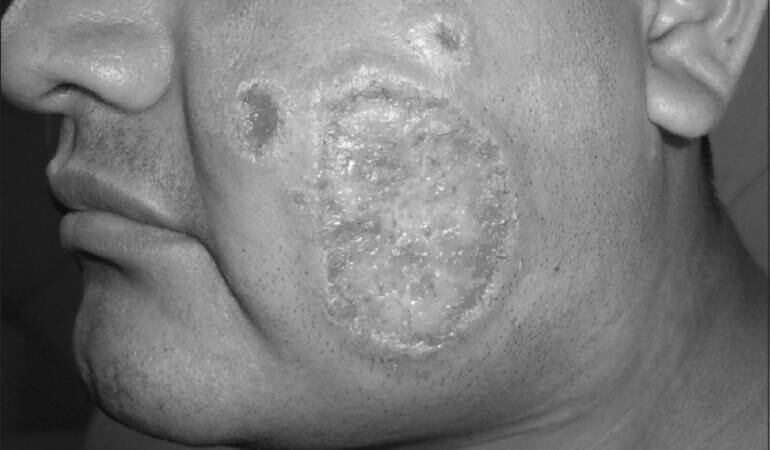

(Foto http://www.odermatol.com/)

La leishmaniasis es un conjunto de enfermedades zoonóticas y antroponóticas causadas por protozoos del género Leishmania. Las manifestaciones clínicas de la enfermedad van desde úlceras cutáneas que cicatrizan espontáneamente, hasta formas fatales en las cuales se presenta inflamación grave del hígado y del bazo.